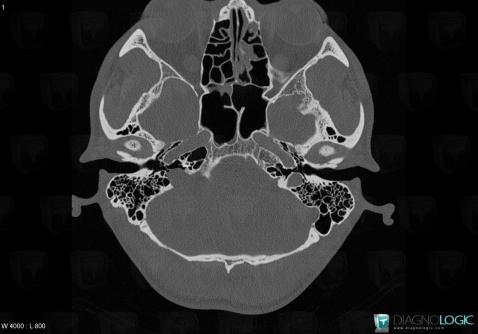

Schwannome, Os temporal, Scanner

Voici les informations spécifiques à l'image clé ci dessus:

- Diagnostic Schwannome, Localisation(s) Os temporal, comportant les gammes Lésions de l'apex pétreuse, Ostéolyse de l'oreille moyenne ou de la mastoide